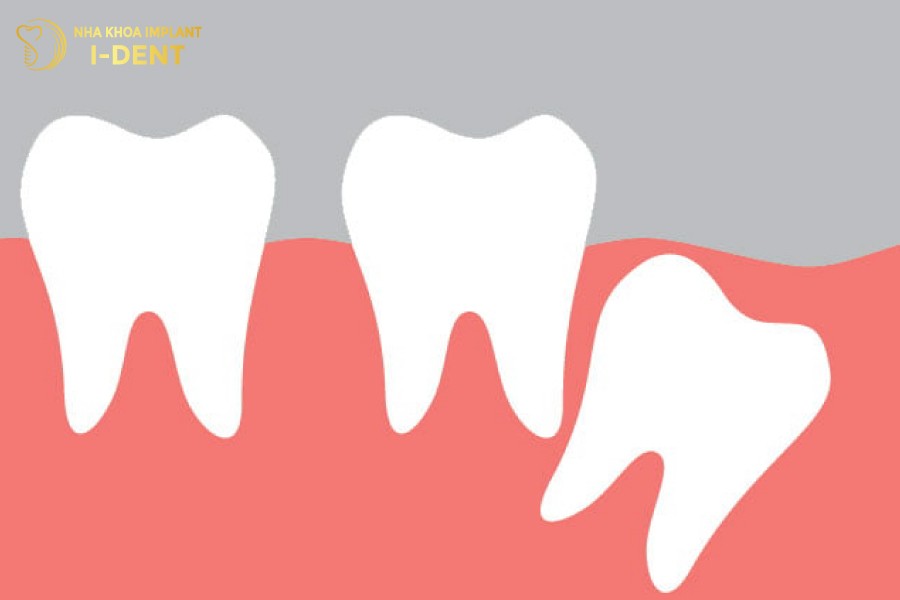

1.4 Răng khôn mọc ngang

Răng khôn mọc ngang là tình trạng răng khôn nằm ngang, chạm vào các răng kế cận. Xu hướng phát triển của răng là đâm vào răng hàm số 7 kế cạnh, dẫn đến sự hình thành các u nang răng, thậm chí có thể gây hỏng răng số 7 nếu không nhổ răng khôn nằm ngang kịp thời.

Răng khôn mọc ngang